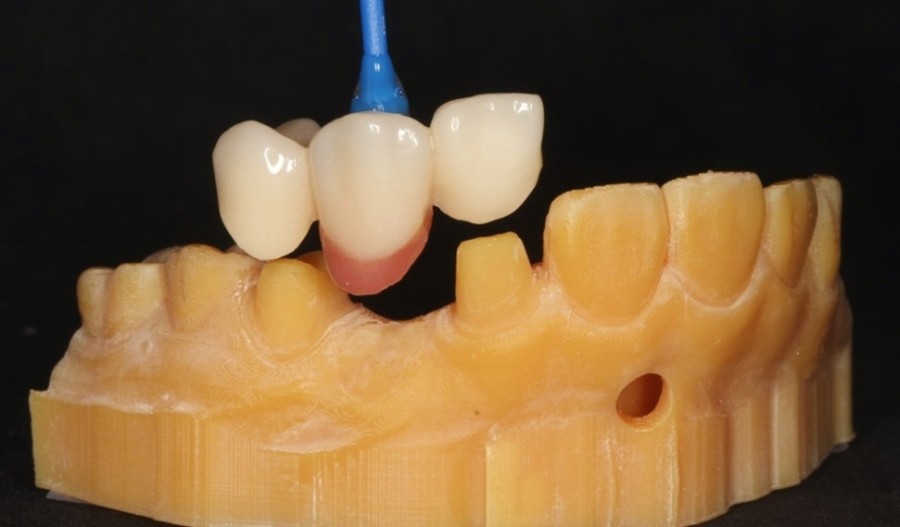

미니쉬치과병원에서는 먼저 3D 구강 스캔 후 디지털 정보로 전환하여 나에게 가장 적합한 치아 모양을 디자인하게 됩니다.

이러한 과정은 자연치아와 경계 부위를 틈새없이 정밀하게 밀착시켜 오랜기간 사용하기 위함인데요.

본뜨는 과정에서 발생하는 재료변형의 오차를 줄이면서 개개인의 치아 형태에 맞춤으로 제작이 가능해 내게 가장 어울리는 아름다운 치아를 가질 수 있습니다.